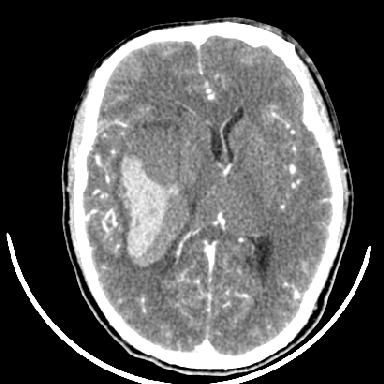

考虑高血压性脑出血,依据:

1是高血压性脑出血的好发部位,形态呈肾形,是高血压性脑出血的常见形状

2增强时占位效应加重了,考虑出血还没有停止

3病灶周围水肿不是太厉害,一般肿瘤出血水肿多非常明显

4病灶周围的‘软组织’影没有明显的强化

5至于脑血管畸形引起的出血,暂时没有看到明显的畸形血管影,也不太支持

但脑出血早期做增强是不是有点太冒险了?

术中抽出40ml陈旧血液,血肿底部似见一条索血管影